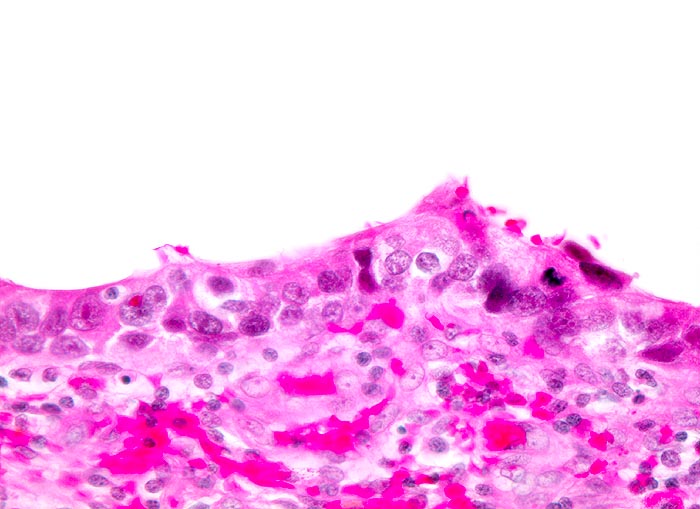

Carcinoma in situ des Urothels

Verschmälertes Urothel. Deutlich ausgeprägte Zellkernpolymorphie. Starke Vergösserung der hyperchromatischen Kerne mit Verschiebung der Kern-Zytoplasmarelation.

Invasives Plattenepithelkarzinom der Harnblase.

Histologie

320